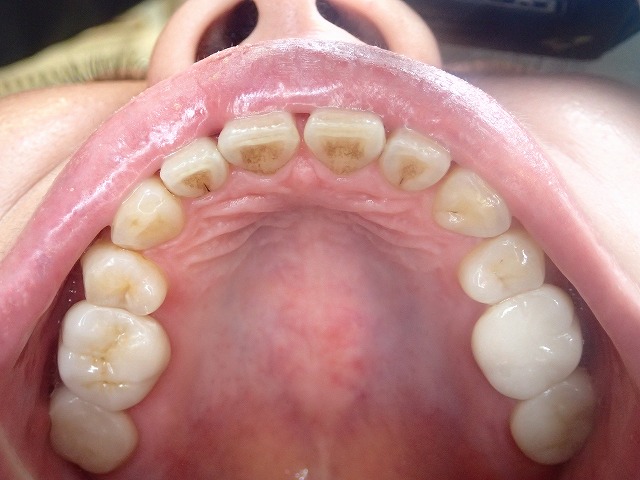

20代でも激しい歯ぎしりのある方が

最近増えたような気がしています。

この方の場合にはエナメル質はすでに消失しており

象牙質が露出しているので

食事などの際に痛みを感じるようになっています。

激しい歯ぎしりにより、奥歯のエナメル質が消失

象牙質が露出すると、摩耗は加速度的に進行する

すでに手前の大臼歯はジルコニアクラウンで対策してありますが

その奥の歯も、大きく摩耗して

象牙質が露出した場合には

減り方が加速しますので対策が賢明です。

手前のジルコニアクラウンは

光の関係で、一部丸く透けて見えますが

別画像を見てください。

まったく問題ありません。